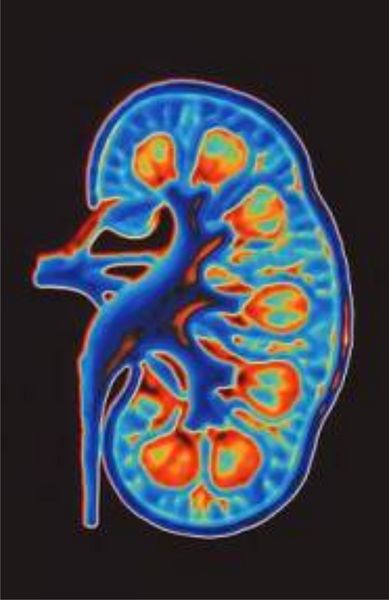

Den Nieren kommen ganz wesentliche Aufgaben bei der Aufrechterhaltung des Inneren Milieus zu: sie reinigen das Blut von schädlichen Stoffwechselprodukten und von mit der Nahrung oder als Medikamente aufgenommenen Schadstoffen; sie regulieren den Salz- und Wasserhaushalt und somit den Blutdruck; sie regen die Blutbildung an. Jeden Tag werden in den Nieren etwa 180 Liter Wasser filtriert. Mit dem Wasser werden auch etwa 1,5 kg Kochsalz und 150 g Zucker filtriert. Von diesen enormen Mengen werden normalerweise 99 % in den Nierenkanälchen wieder zurück gewonnen. Diese enorme Transportarbeit der Nieren ist notwendig, um ein Austrocknen des Menschen und den Verlust von wichtigen Salzen und Nährstoffen zu verhindern. Wichtige Stoffe wie Natriumchlorid, Zucker oder Aminosäuren gelangen zurück in den Blutkreislauf, ebenso das meiste Wasser. Stoffe, die tatsächlich ausgeschieden werden müssen, werden dagegen im Harn angereichert. Für die Rückgewinnung und Ausscheidung dieser Substanzen sind besondere Transportproteine in den Zellmembranen der hoch spezialisierten Nierenzellen, so genannte Transporter, Pumpen und Kanäle, verantwortlich. Diese Transportvorgänge werden in komplexen hormonellen Steuerkreisen geregelt und den jeweiligen Bedürfnissen angepasst. Störungen in diesen Vorgängen, die genetisch bedingt oder erworben sein können, führen zu gravierenden Auswirkungen auf den ganzen Organismus bis hin zu lebensbedrohenden Zuständen, die eine künstliche Blutwäsche (Dialyse) oder eine Nierentransplantation notwendig machen.

In der Experimentellen Nephrologie werden die Funktion und Regulation von einigen dieser Transportproteine (wie z.B. Ionenkanäle, Wasserkanäle, organische Kationentransporter) unter normalen und pathologischen Bedingungen (z.B. unter Abstoßung nach Nierentransplantation) oder deren Beteiligung an nierenschädlichen Nebenwirkungen von Medikamenten untersucht. Hierzu werden verschiedene experimentelle Tiermodelle, Zellkultursysteme und humanes Gewebe verwendet und mit modernen Methoden der Zellbiologie, der Molekularbiologie, der Elektrophysiologie, der Fluoreszenzmikroskopie und der Bildgebung untersucht. Näheres hierzu finden Sie hier.